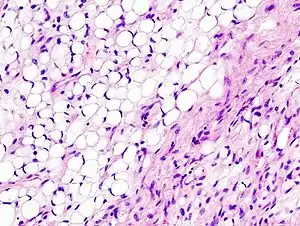

Histopathologically, ALT/WDL tumors are divided into adipocytic/lipoma-like, sclerosing, and inflammatory variants with adipocyte/lipoma-like being the most common. Adipocytic/lipoma-like ALT/WDL tumors consist of lobules of mature fat cells variably intersected with irregular fibrous septa (see the adjacent H&E stained photomicrograph). Sclerosing ALT/WDL tumors, the second most common variant, develop primarily in the retroperitoneal and paratesticular areas; it consists of scattered, atypical stromal cells within a collagenous (i.e. collagen-containing) stromal tissue background. Rare vacuole-containing lipoblasts populate this tissue. Inflammatory ALT/WDL tumors are the rarest variant. they occur most frequently in the retroperitoneum and consists of chronic inflammatory cells, e.g. lymphocytes and plasma cells plus occasional lymph node-like follicles interspersed throughout a tissue background containing fat cells.[14]